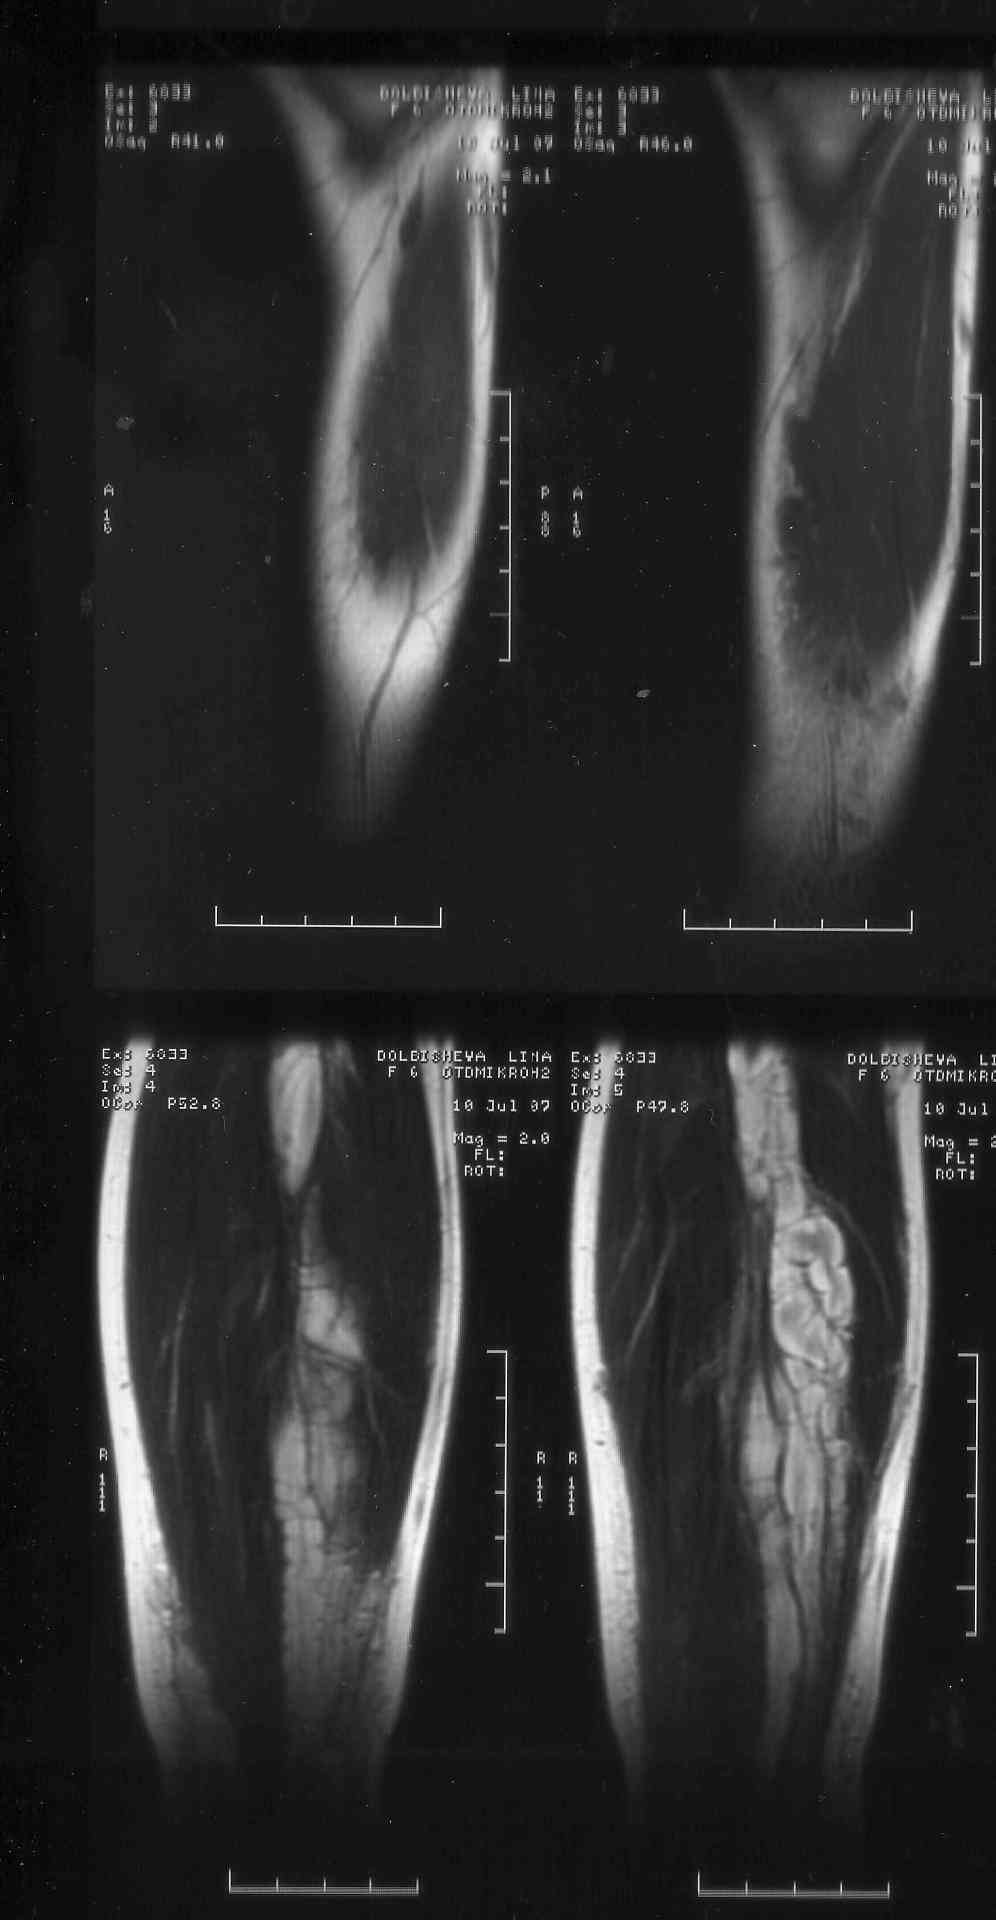

Обратились по поводу удлинения голени и деформации голенностопного сустава . В процессе обследования на МРТ выявлен нейрофтброматоз. Локализация процесса протяженная -от с\3 бедра до г\стопного сустава. Сонографически узлы распологаются как внутриствольно так и рядом.Если в стране специализированные центры и какая тактика была выбрана бы вами. Заранее благодарен за помощь.

Неврологических нарушений нет. Клинически -удлинение костей голени на 2 см и утолщение их , г\стопный сустав увеличен в размерах и несколько деформирован за счет наличия нейрофибром в мягких тканях. Диагноз подтвержден гистологически (удаление фибром в обл г\ст сустава) . Девочка активна и очень интелектуально развита.